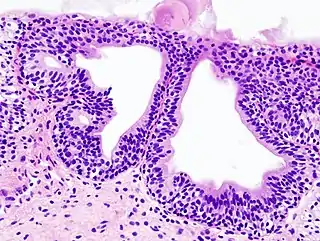

![]() Histopatología de una cistitis glandular en una biopsia citoscópica. Tinción con hematoxilina y eosina. | ||